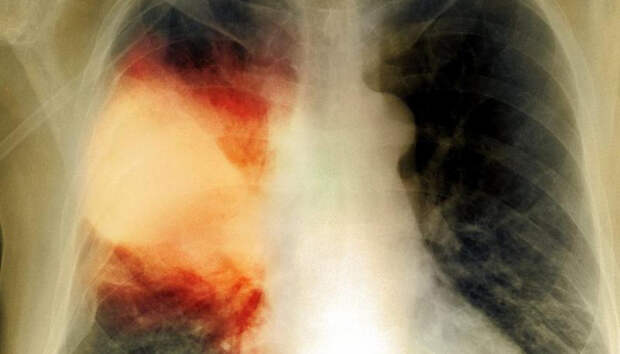

Всем пациентам с пневмонией неоднократно проводится исследование на COVID-19 За минувшие сутки в Карелии госпитализированы одиннадцать человек с внебольничной пневмонией. Такие данные приводит оперативный штаб по борьбе с коронавирусом. Летальных исходов за сутки не зафиксировано. Начиная с 1 апреля, с внебольничной пневмонией госпитализированы 755 пациентов, 62 человека умерли (с учетом пациентов, госпитализированных ранее указанного периода).